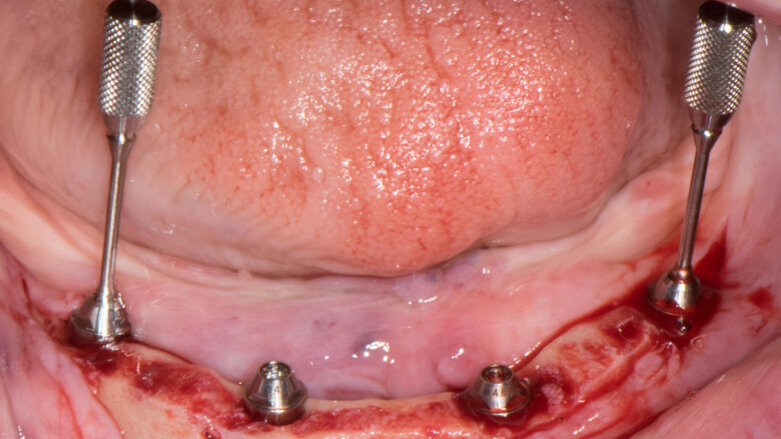

Because of an open-flap procedure owing to the lack of keratinised tissue and the placement of long implants (all Straumann BLT Roxolid, SLA implants; 4.1 × 12.0 mm), it was decided to make two surgical guides: first, a mucosa-supported guide only for drilling the template fixation pins (Straumann; Fig. 7); and second, a pin-supported guide for fully guided implant placement (Fig. 8).

Implant beds were prepared (Figs. 13 & 14) and Straumann BLT implants placed with a torque setting of more than 35 Ncm, following the protocol to allow correct subsequent screw retained abutment placement (Figs. 15 & 16). Bone around the implants was prepared with bone profilers (Straumann) for the same reason (Fig. 17). The crest was flattened (Figs. 18 & 19), screw-retained abutments were screwed to 35 Ncm (Fig. 20) and covered with healing caps, and the wound was sutured (Fig. 21).